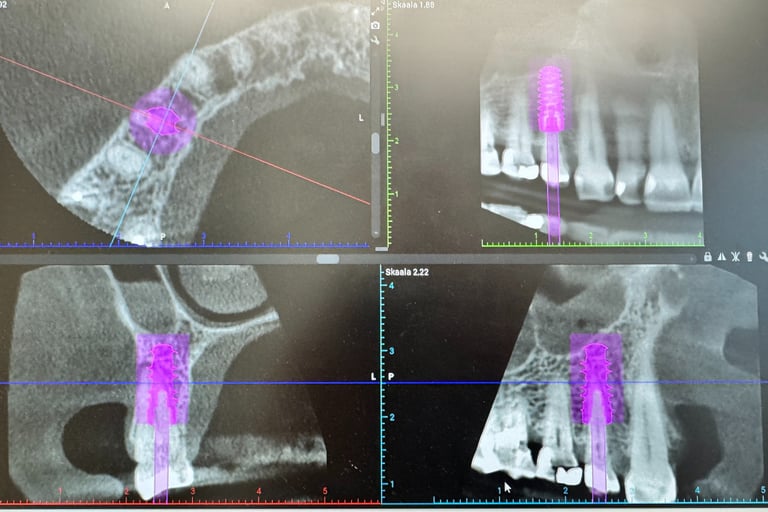

Hammasimplantti on titaaninen tai keraaminen 'ruuvi' joka asetetaan luuhun. Tämän varaan voidaan valmistaa yksilöllinen hammas.

Mielestäni kyllä. Ja siksi käytän vain Straumann -implantteja. Niiden avulla saadaan paras mahdollinen rakenne ennustettavalla luutumisella. Myös tärkeää on että tulevaisuudessa on osia tarvittaessa saatavana. Maailmassa on noin 600 eri implanttimerkkiä käytössä ja olen valinnut Straumann implantit juuri näistä syistä. Straumann implantit on olleet kymmeniä vuosia markkinoilla ja tutkimus niiden osalta on perusteellista.